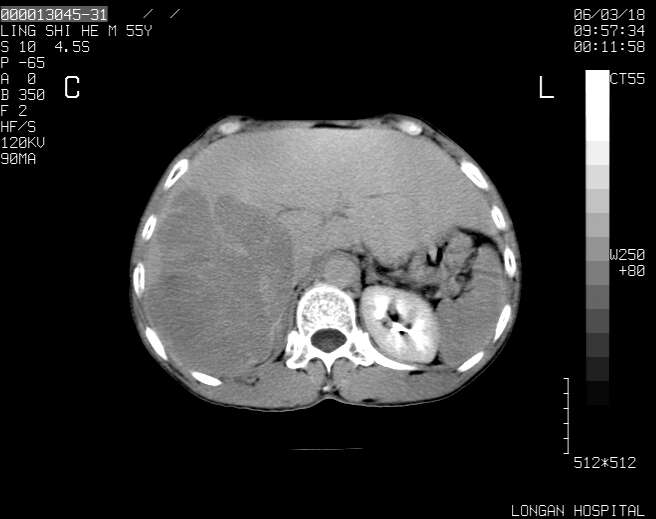

以下是引用guzhongliangddd在2006-3-21 22:13:00的发言:[br]病灶主要位于肝右叶的后份,内见异常血管,门脉主干及右支受侵{提示有癌栓形成},门腔间隙内见增大淋巴结。肝左叶内未见异常。

以下是引用zhuxinli在2006-3-22 1:23:00的发言:[br][br] 病灶主要位于肝右叶的后份,内见异常血管 .门脉右支截断,右叶前段早期强化(考虑动静脉漏),腹膜后肿大淋巴结,病灶逐渐强化,考虑为胆管细胞癌[br]